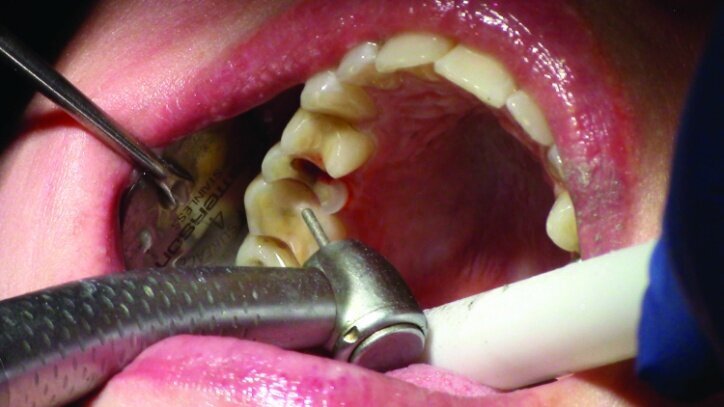

This patient presented for restorations of teeth #3 and #4 (Fig. 1a). Because of the size of the existing restorations, these teeth were diagnosed as structurally compromised (Figs. 1b, c). The prognosis without treatment was fair.

The restorations were to be completed with PlanScan chairside CAD/CAM technology in the same visit.

Depth guide cuts were made using a 330 bur, which has a 2 mm cutting surface (Figs. 2a–3b). This ensures 2 mm of occlusal reduction to accommodate 2 mm of material thickness on the occlusal surface of the restoration.